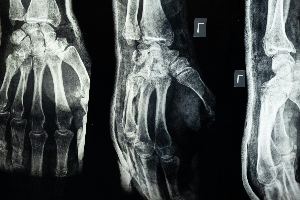

4-3.영상 검사: X-ray, MRI, 초음파 등을 통해 관절의 상태와 손상을 평가합니다. 이러한 검사는 관절의 구조적 손상을 확인하는 데 도움을 줍니다.